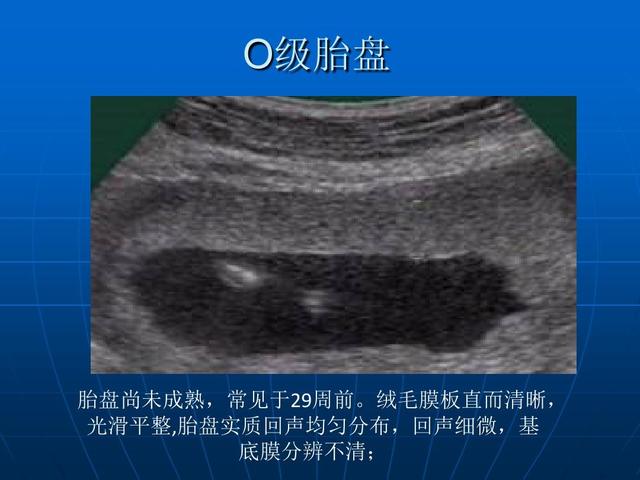

胎盘成熟度分为0级、1级、2级、3级 , 也会写作胎盘分级 , 一般会用罗马数字来表示 。 我26周和32周的胎盘成熟度都是0级 , 到了38周 , 胎盘成熟度忽然变成了2级 , 第二天就分娩了 , 胎盘成熟度也在提示胎儿成熟度 。

胎盘成熟度0级:说明胎盘还没有成熟 , 一般在12-28周 。